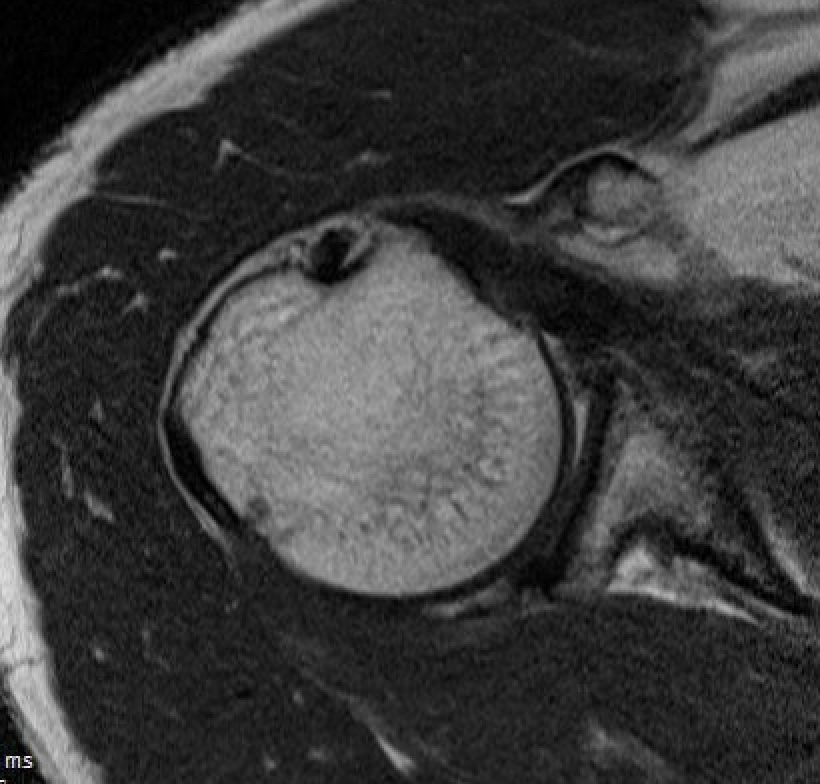

Tendonitis / tendinopathy

Normal

Tendonitis

Tendon thickening / tendinopathy

Sagittal MRI demonstrating severe LHB tendinopathy